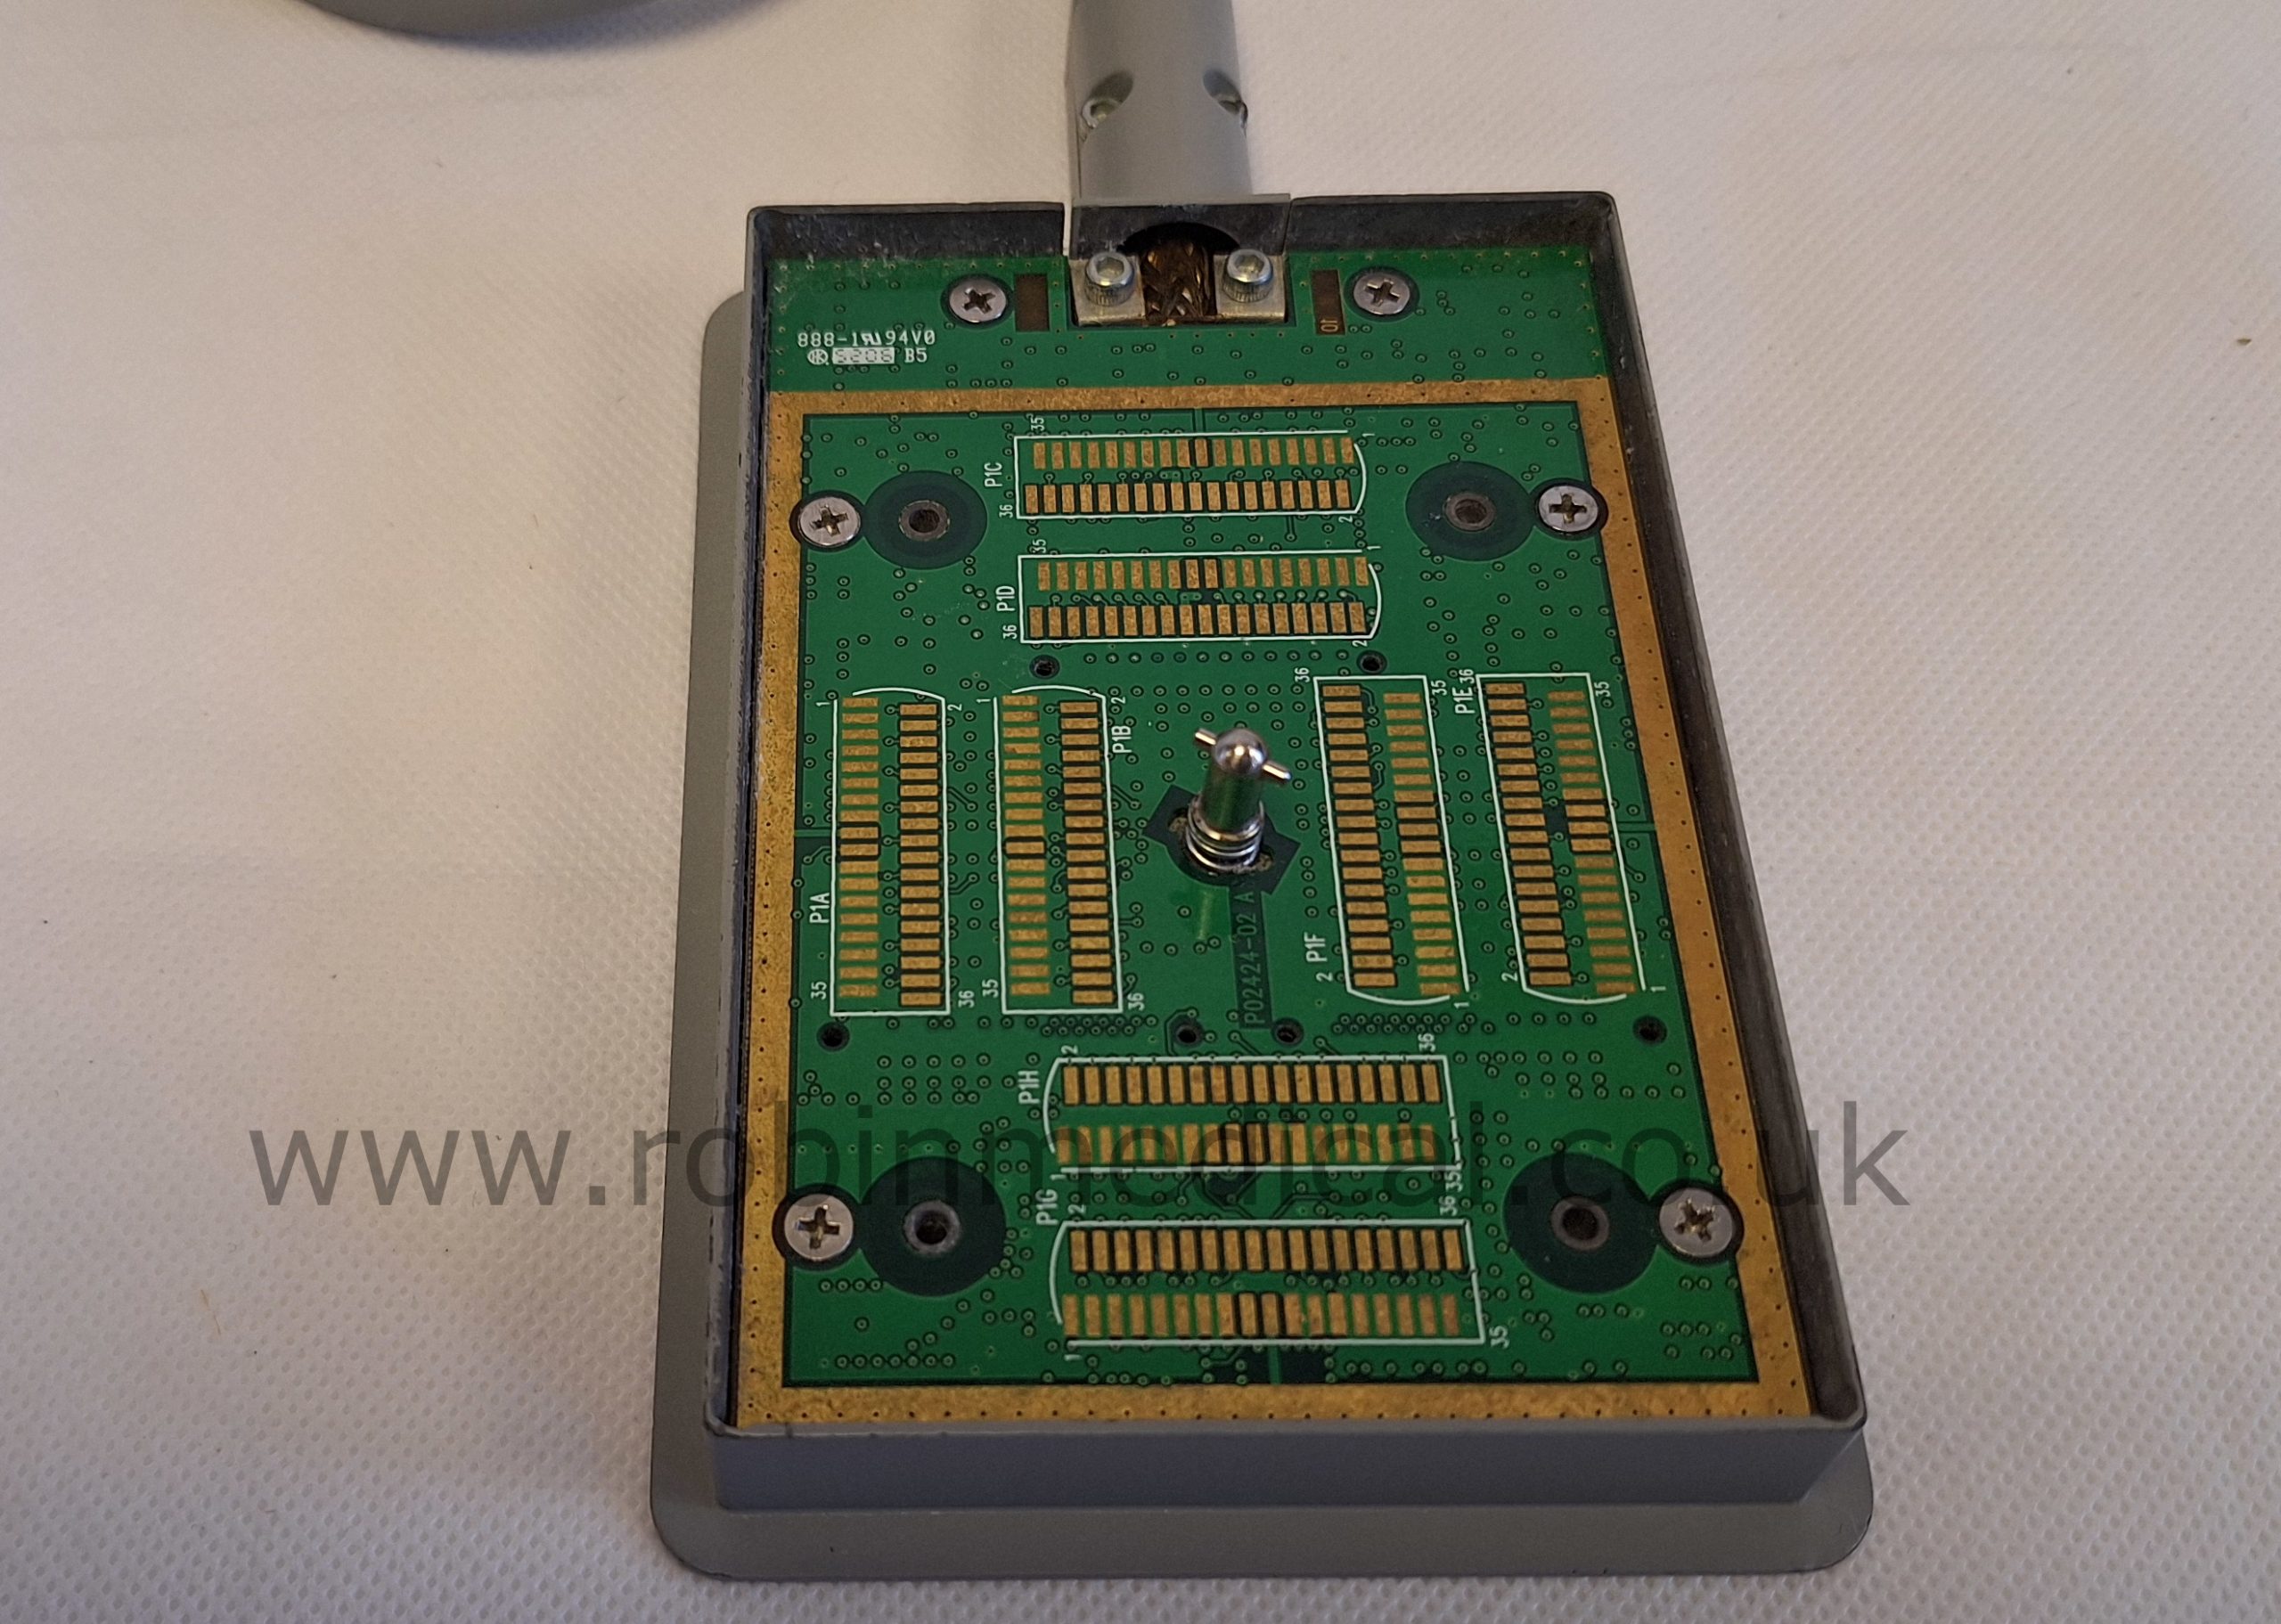

The probe functions as intended and the condition is exactly as shown in images.